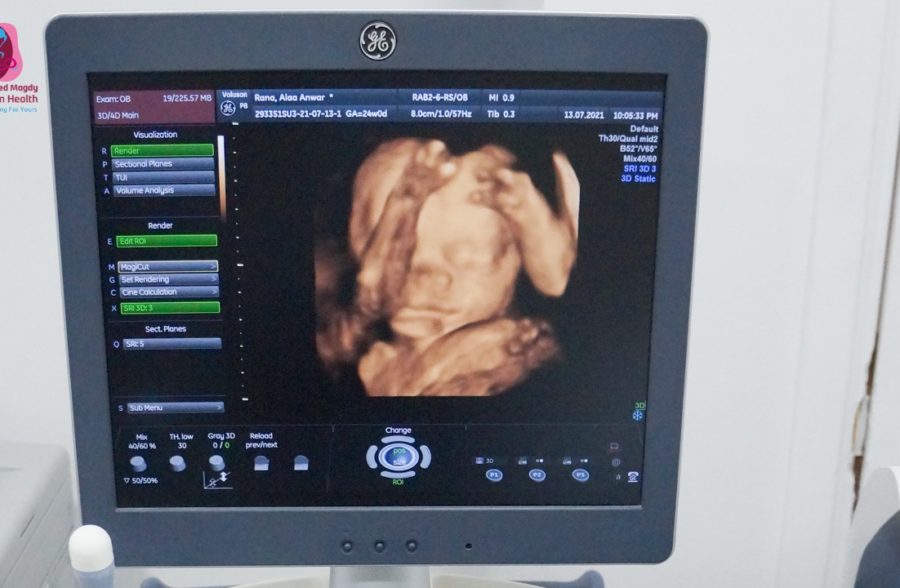

– 3D & 4D ultrasound for detection of fetal well being.